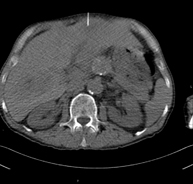

- TC Abdomen

Prova diagnòstica que consisteix en l'estudi de l'abdomen d'alta definició anatòmica (fetge, vesícula biliar, via biliar, pàncrees, melsa, estómac, intestins, ronyons, estructures vasculars, bufeta, úter i ovaris, etc.) mitjançant l'ús d'un equip de TC (Tomografia Computeritzada). Aquestes imatges s'estudien posteriorment en una estació de treball que permet obtenir reconstruccions bidimensionals en diferents plànols de l'espai i també reconstruccions 3D (volumètriques). La majoria d'estudis requereixen l'ús de contrast iodat per millorar la definició de les imatges. - TC Pelvis